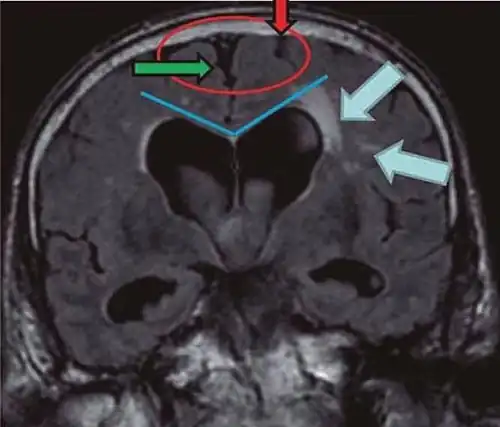

• Imaging from magnetic resonance imaging (MRI) or computed tomography (CT) is needed to demonstrate enlarged ventricles and no macroscopic obstruction to cerebrospinal fluid flow. Imaging should show an enlargement to at least one of the temporal horns of lateral ventricles, and impingement against the falx cerebri resulting in a callosal angle ≤ 90° on the coronal view, showing evidence of altered brain water content, or normal active flow (which is referred to as "flow void") at the cerebral aqueduct and fourth ventricle.

Typical imaging findings in normal pressure hydrocephalus versus brain atrophy.[21]

Normal pressure hydrocephalus Brain atrophy

Preferable projection Coronal plane at the level of the posterior commissure of the brain.

Modality in this example CT MRI

CSF spaces over the convexity near the vertex (red ellipse ) Narrowed convexity ("tight convexity") as well as medial cisterns Widened vertex (red arrow) and medial cisterns (green arrow)

Callosal angle (blue V) Acute angle Obtuse angle

Most likely cause of leucoaraiosis (periventricular signal alterations, blue arrows ) Transependymal cerebrospinal fluid diapedesis Vascular encephalopathy, in this case suggested by unilateral occurrence

MRI scans are the preferred imaging. The distinction between normal and enlarged ventricular size by cerebral atrophy is difficult to ascertain. Up to 80% of cases are unrecognized and untreated due to difficulty of diagnosis.[22] Imaging should also reveal the absence of any cerebral mass lesions or any signs of obstructions. Although all patients with NPH have enlarged ventricles, not all elderly patients with enlarged ventricles have primary NPH. Cerebral atrophy can cause enlarged ventricles, as well, and is referred to as hydrocephalus ex vacuo. For these reasons it's utmost important to note that Evan's index although commonly used in imaging is not very specific for NPH. One recent systematic review and meta-analysis suggests that callosal angle has high diagnostic performance and is commonly used together with Evan's index.[23]